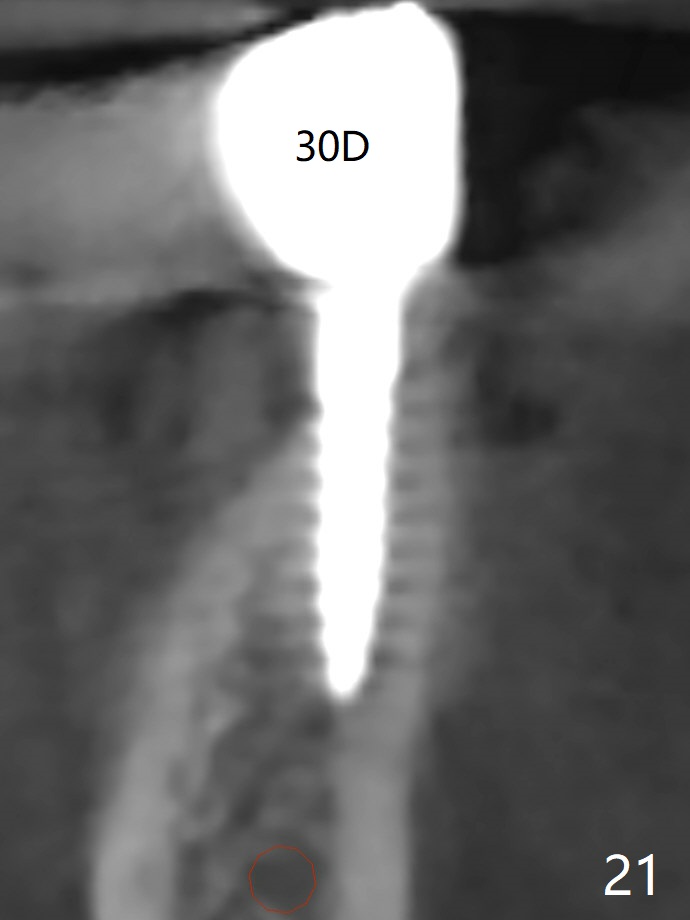

Two of 2.5 mm 1-Piece Implants M

The edentulous ridge at #30 is narrow (Fig.1). After ridge reduction, osteotomy is initiated with 1.2 mm drill for 10 mm; the mesial osteotomy is to be changed (Fig.2 red line). Using a 1.2 mm drill placed in the distal osteotomy (Fig.3 D), the mesial osteotomy changes in trajectory with subsequent placement of a 2.5x10(4) mm 1-piece implant. Since the mesial implant is high in occlusion, the cuff of the distal implant is changed to be 2 mm (Fig.4 (shorter black line)). Panoramic X-ray is taken to show no violation of the Inferior Alveolar Canal (Fig.5 red dashed line). These two 1-piece implants are slightly lingually placed (Fig.6). The crestal bone around the implants resorbs without thread exposure 5 months postop (Fig.7). Impression is taken for a splinted crown (Fig.8-12). There is no metal show around the 2.5 mm 1-piece implants 6 months postop (advantage) vs. that at #28 and 29 (Fig.13). Bitewing is taken post cementation to determine whether residual cement is present (Fig.14). There is periodic swelling and pain in the lower right quadrant 2 years post cementation (Fig.15). In fact periimplantitis appears to have developed at #28 (Fig.16) with loss of the buccal bone (Fig.17,18). The buccal bone loss is less at #29 (Fig.19) and #20 (Fig.23) and no at #30 mesial and distal implants (Fig.20,21). A much smaller implant will be placed lingually at #28 immediate (Fig.24,25).